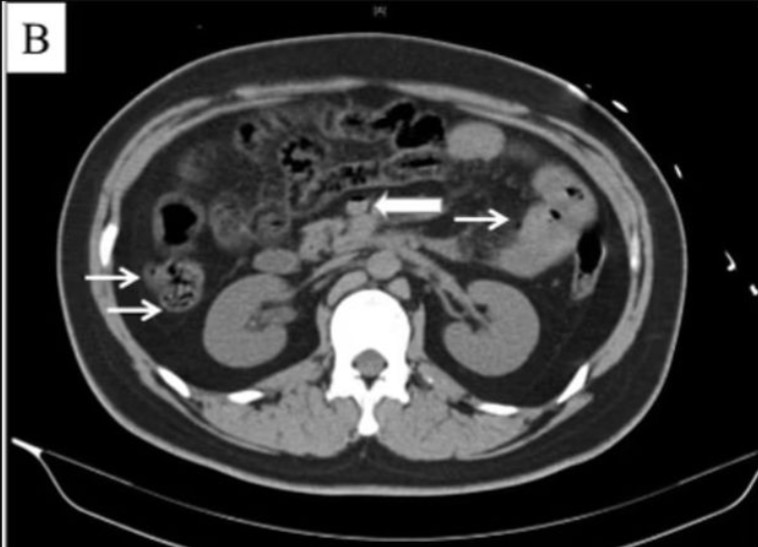

צילום ה-CT של המטופל - B

צילום ה-CT של המטופל - B | צילום: Chaoyang Hospital

כמו כן, בדיקת CT בכבד חשפה כי אותו הבחור סבל מאיסכמיה בכבד, שהיא מעין פגיעה הנגרמת כתוצאה מאספקת חמצן נמוכה לאיבר. המחבר הראשי של דו"ח המקרה, 'צאינג הו, הסביר כי הרופאים ניסו לנקז את הגז ממערכת העיכול של בן ה-22, אך בצער הוא לא הצליח לשרוד את הטיפול והלך לעולמו אחרי 18 שעות מתחילת ההליך הרפואי.